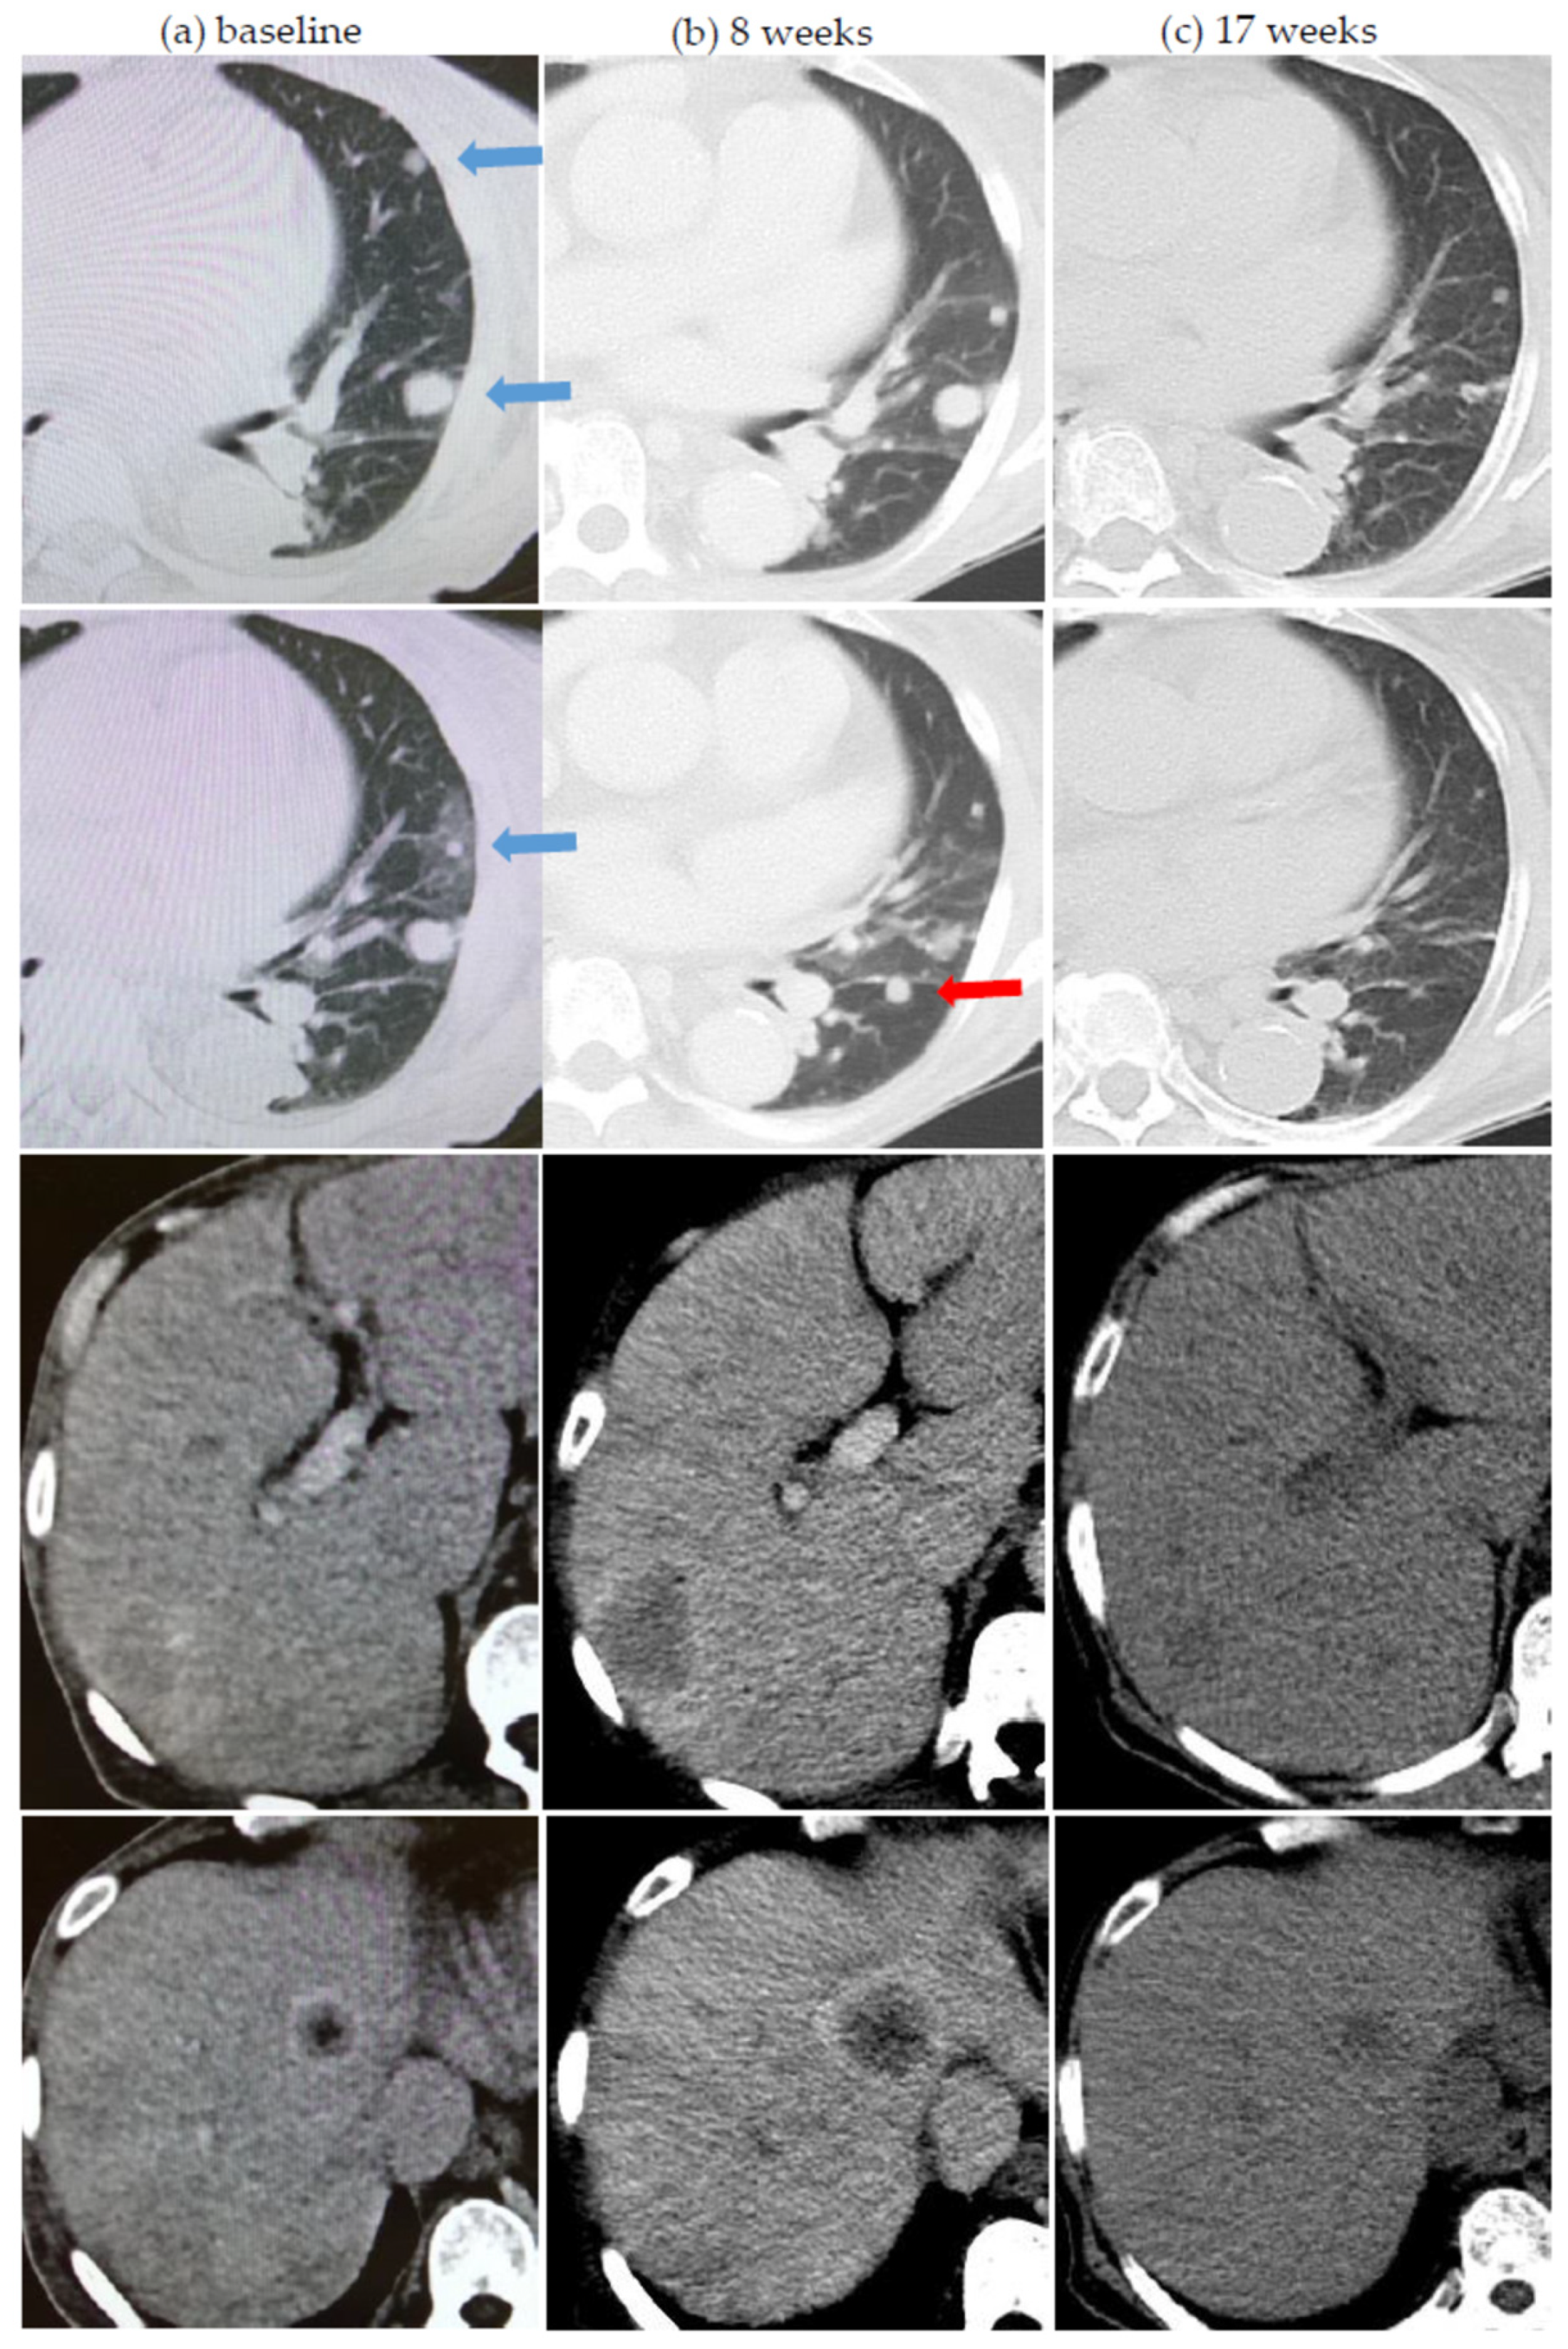

| Serial pseudoprogression | 2 | 13.3 | 2 | 6.5 | 4 | 8.7 |